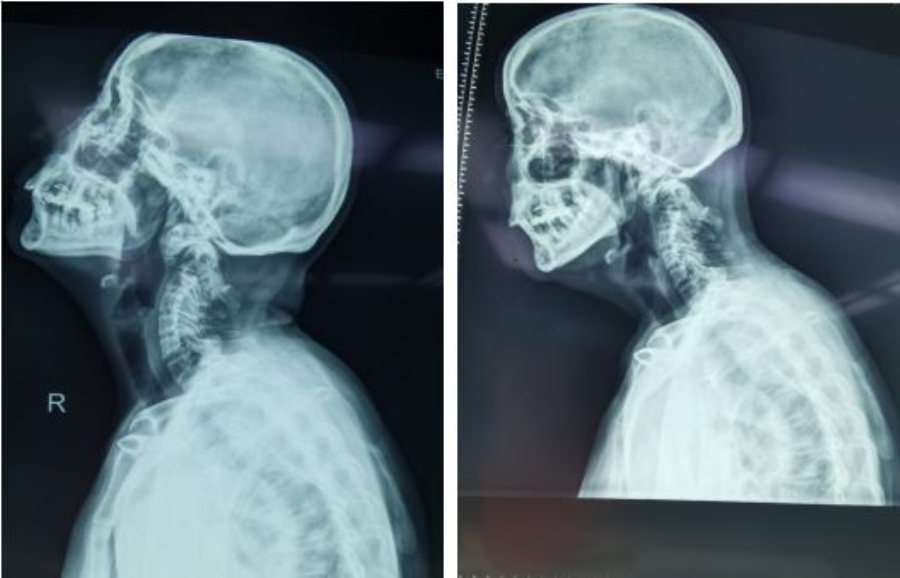

患者67岁,4个月前无明显诱因出现四肢麻木僵硬无力,不能自行站立、行走,曾行针灸治疗效果不明显,且症状逐渐加重。在进一步寻求诊疗的过程中,于今年年初慕名来91直播 找到颈椎外科张沛主任就诊。张主任结合颅脑和颈椎的相关检查,经阅片查体后诊断为“1、寰枢椎脱位;2、先天性齿状突发育不良;3、慢性脊髓病”而收入住院治疗。

术前X光片